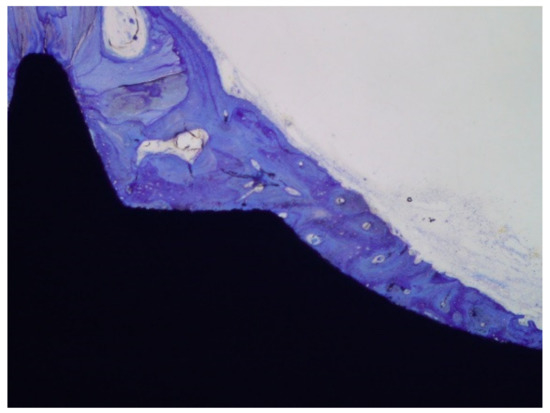

Klockner’s dental implantations were performed on pigs at different times of osseointegration. In Figure 11, the thermochemical treatment (2S) can be observed, showing that the sodium titanate had a good osseointegration at 4 weeks after implantation. This value is compared with other surface treatments (R: roughened by blasting; E: acid attack; Ctr: control). These values show an acceleration of bone in-growth around the dental implant, which was already significant 2 weeks after implant placement. These implants provided excellent primary fixation, even before the hard tissues started to significantly regenerate. These osseointegration levels evidenced the good short-term in vivo performance of the treated surfaces in comparison with the other conventional implants tested. Osseointegration was accelerated and, consequently, implant failure decreased. Figure 12 indicates the osteoconductive behavior of the thermochemically treated surface two2-step), where it can be observed that the new bone is growing from the surface of the implant [44,45,46].

The histologies show how the implant surface facilitates the formation of bone, as shown in Figure 12 and Figure 13, and where bone is formed from the implant surface with sodium titanate. With this, an osteoinductive effect is achieved that favors the reduction in osseointegration time [47,48,49,50].

Figure 13. Histology at 2 weeks after implantation. (a). Dental implant with an osseointegration of approximately 70% after two weeks of implantation. (b). At higher magnification showing the implant-bone tissue interface.